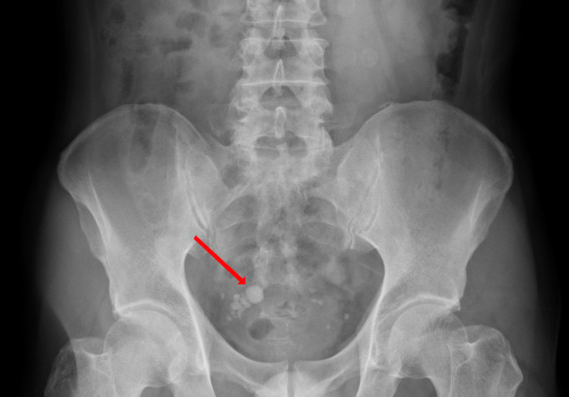

⑧ 방광결석

소변 속의 무기질이 응고되어 결석이 생기면 방광점막이 자극을 받아 염증과 통증이 생기며, 이는 방광기능 저하로 이어질 수 있습니다. 잔뇨나 혈뇨도 동반됩니다.